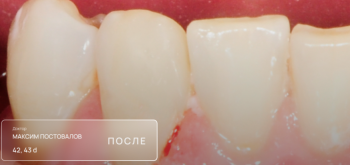

Постовалов Максим Юрьевич

Постовалов Максим Юрьевич принимает в «Стоматологическая клиника ОПТИМА С» в Перми. Стаж 6 лет. Специализируется на терапии, по которой клиника оказывает 8 услуг. Имеет 12 работ до/после в портфолио. Также 32top представляет форму онлайн расписания, через которую можно записаться к специалисту на свободную дату и время.

12 работ в портфолио